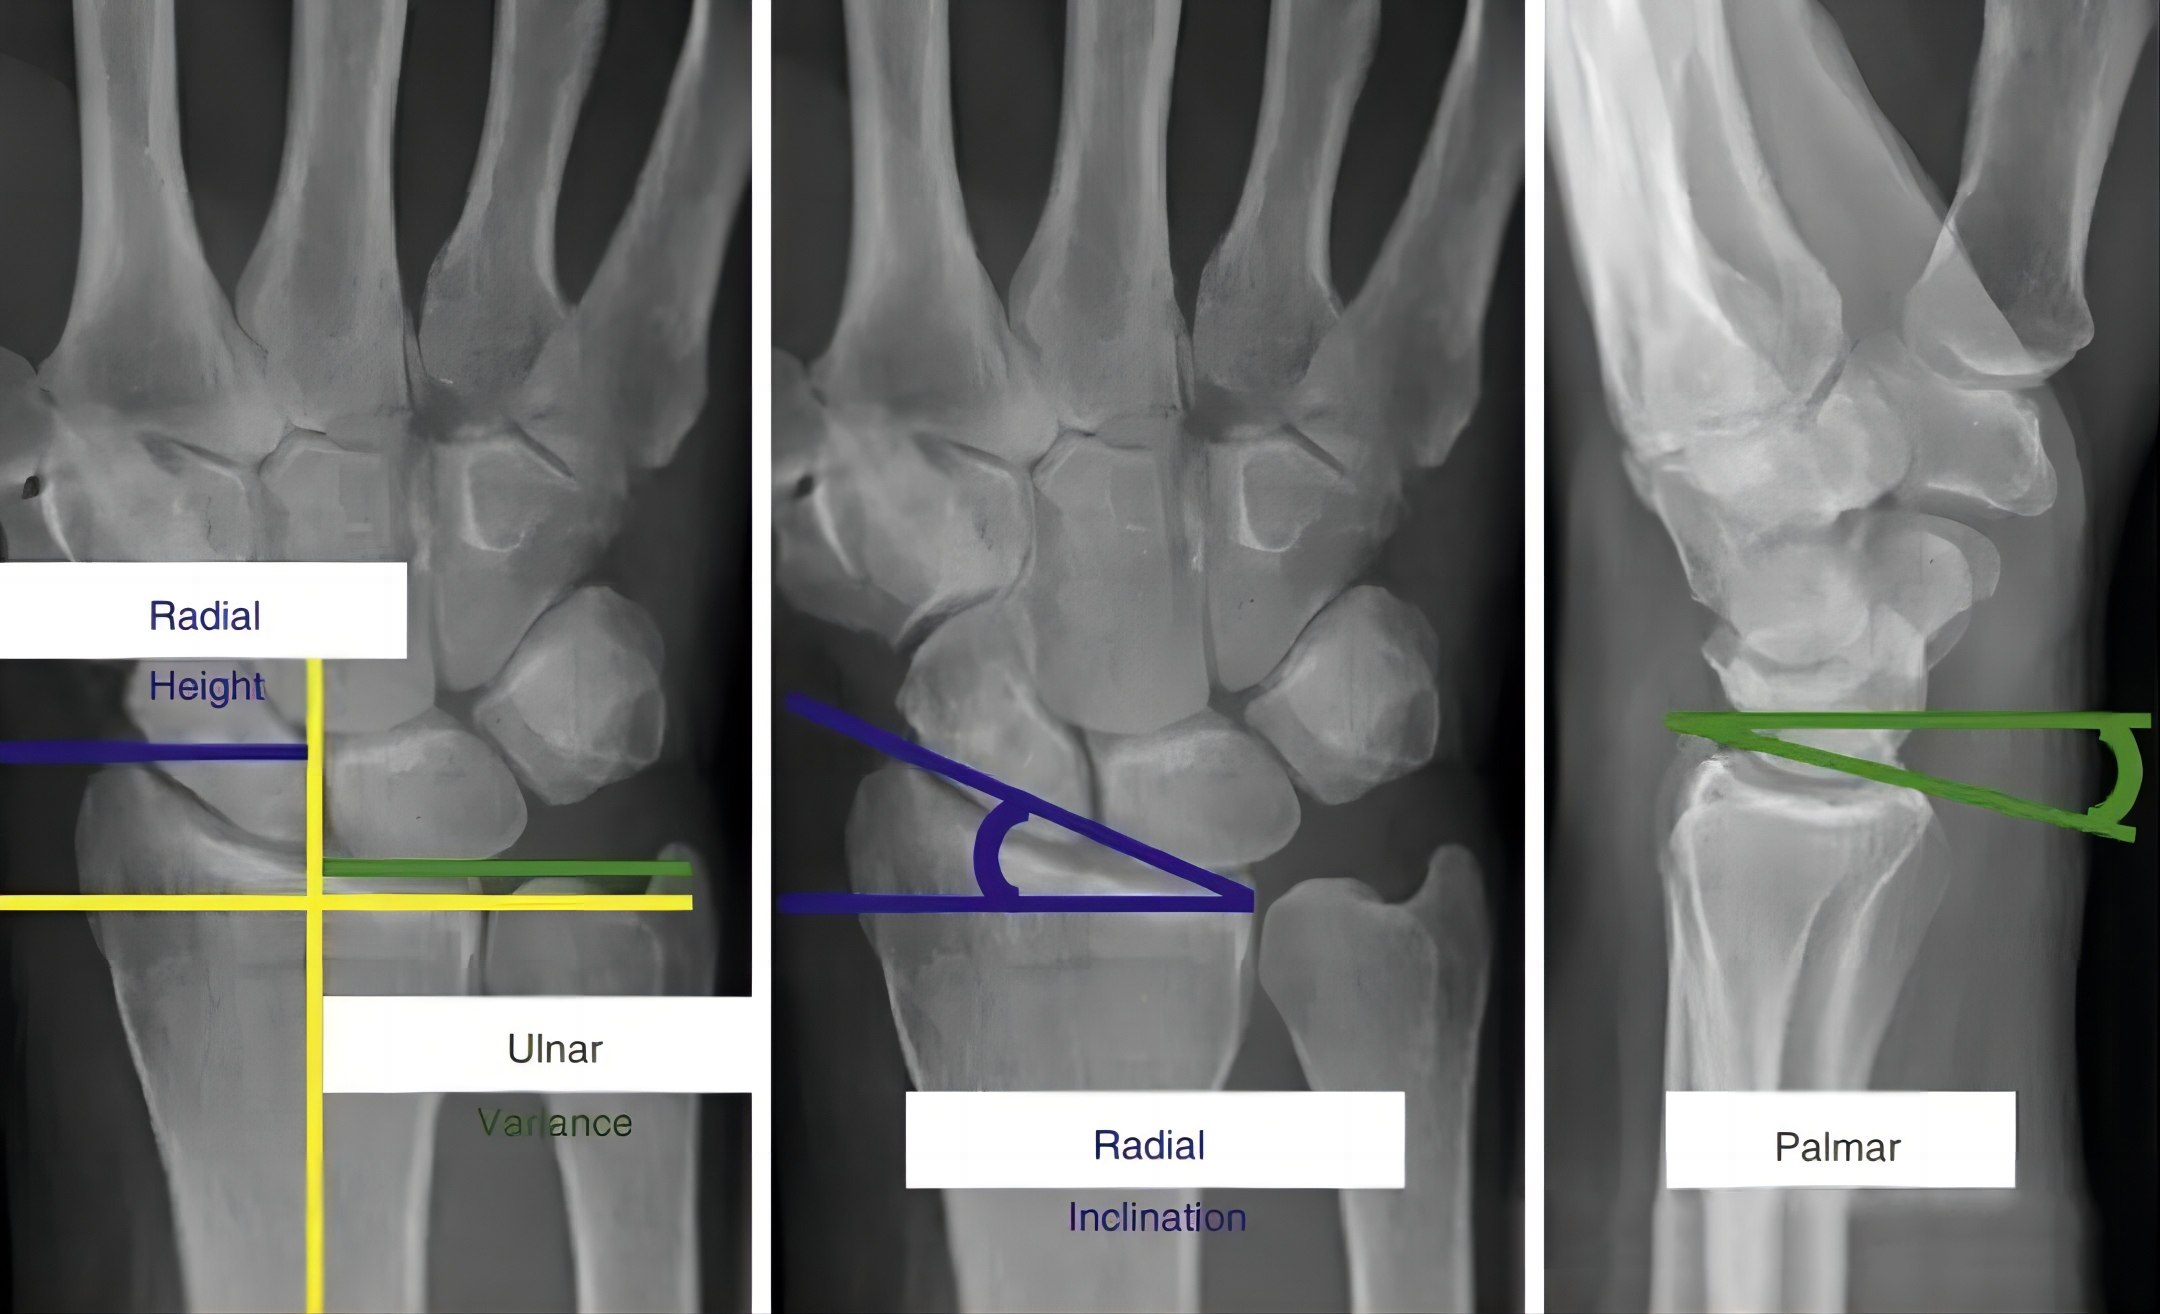

Измерение параметров визуализации дистального отдела лучевой кости (Источник: «Оперативные методы ортопедической травматологии»).

Нормальные параметры визуализации дистального отдела лучевой кости и допустимые диапазоны параметров редукции переломов.